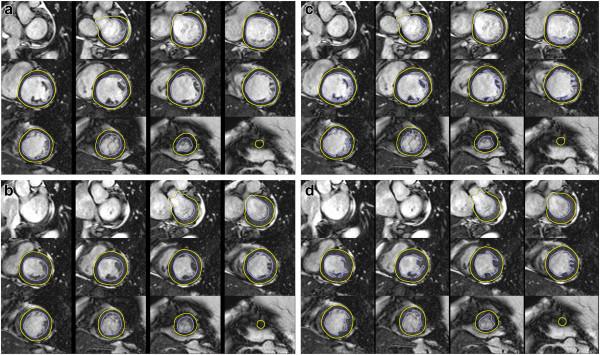

Standardized image interpretation and post processing in cardiovascular magnetic resonance: Society for Cardiovascular Magnetic Resonance (SCMR) board of trustees task force on standardized post processing.

With mounting data on its accuracy and prognostic value, cardiovascular magnetic resonance (CMR) is becoming an increasingly important diagnostic tool with growing utility in clinical routine. Given its versatility and wide range of quantitative parameters, however, agreement on specific standards for the interpretation and post-processing of CMR studies is required to ensure consistent quality and reproducibility of CMR reports. This document addresses this need by providing consensus recommendations developed by the Task Force for Post Processing of the Society for Cardiovascular MR (SCMR). The aim of the task force is to recommend requirements and standards for image interpretation and post processing enabling qualitative and quantitative evaluation of CMR images. Furthermore, pitfalls of CMR image analysis are discussed where appropriate.